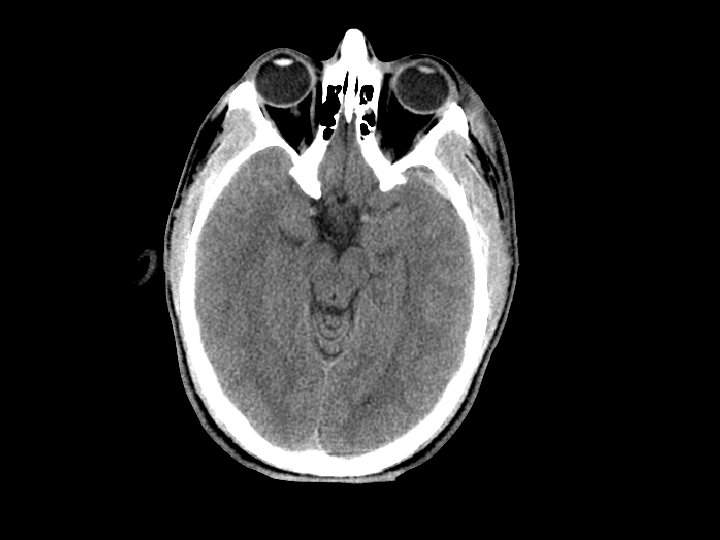

Xét nghiệm chẩn đoán • CT scan: – – – Phương pháp cơ bản Giảm tỷ lệ thương tật và tử vong Đánh giá tình trạng xương và não Nhanh (<1 phút trong CT nhanh) Bệnh nhân bị ăn tia nhiều Chi phí lớn

Chẩn đoán • CT scan: – Bệnh nhân tỉnh và CT bình thường ít có nguy cơ thần kinh xấu đi • Cho ra viện theo dõi – Hạn chế CT: • Không xác định được phù sợi trục lan tỏa • Không xác định được cấp máu cho não